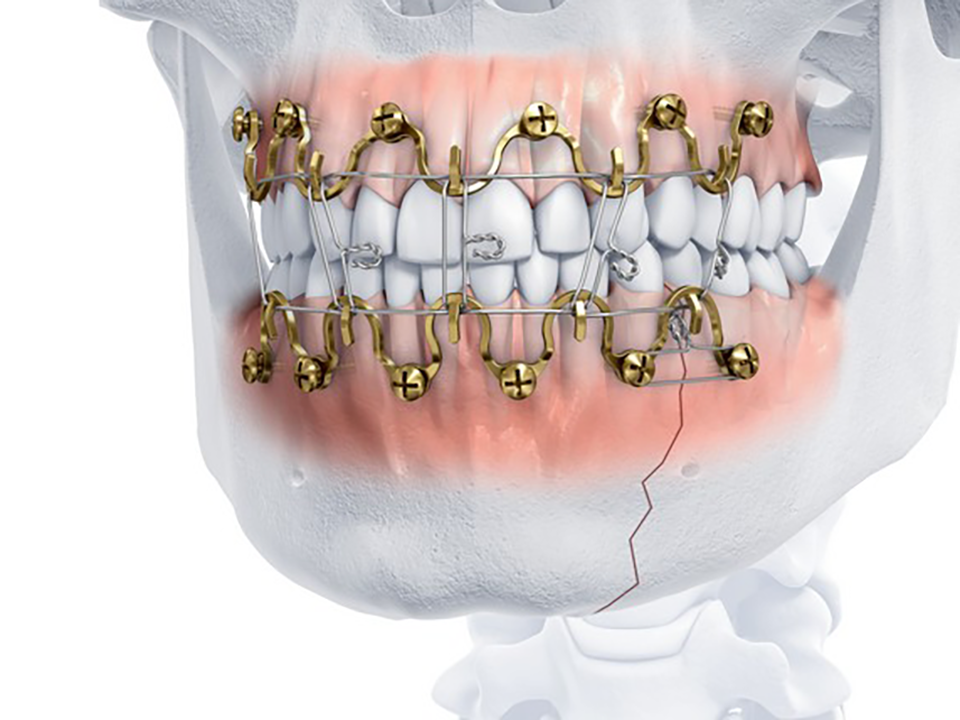

MatrixWAVE MMF (Figs 1-8) is a novel bone-borne MMF system that combines the strength and rigidity of arch bars with the speed and simplicity of IMF screws. It consists of a wave shaped plate that is attached to the mandible and maxilla with self-drilling locking screws (Fig 3). The plate is adaptable and can be extended horizontally (Fig 4) to allow screw hole placement in the optimal location to avoid tooth roots and nerves. The locking mechanism avoids compression and ischemia by keeping the plate away from the mucosal tissues.

The dental arches are brought into occlusion by wiring around the plate hooks and/or accessible screw heads. The self-drilling locking screws sit proud to the plate. This minimizes soft tissue growth over the screw, and provides additional anchor points for optional bridle wires. Upon insertion, screws can be angled at up to 15 to aid in posterior fixation and to optimize dental occlusion.

Following application and wiring, the wave plate pattern allows the alignment of bone segments to be adjusted by crimping without repositioning the screws. The plate is available in two heights to allow the positioning of the hooks at the level of the tooth equators according to individual patient anatomy, and to accommodate the use of rigid internal fixation (Fig 2).

A 28 year old white male was subject to personal assault, and sustained a left mandibular angle fracture (Fig 1). The fracture was prestabilized with the Matrix Wave system and then fixated with a 4-hole miniplate 2.0 on the superior border and a 4-hole angulated universal fracture plate 2.4 along the inferior border. A pre-existing anterior open bite was noted and confirmed with the patient prior to presentation to the operating arena.

The MatrixWAVE plate was attached to the maxilla with screw placement in the inter-root spaces (Fig 2). A second MatrixWAVE plate was attached in corresponding position to the mandible, with screw placement in the inter-root spaces (Fig 3). Wires were placed around the plate hooks to bring the dental arches into occlusion. Note the preexisting anterior open bite (Fig 4). Careful adjustment of the MatrixWAVE plate and wiring in the region of the mandibular fracture allowed the bone fragments to be precisely aligned without the requirement for screw repositioning (Fig 5). The postoperative panoramic x-ray (Fig 6) shows the two MatrixWAVE plates in situ, with other plates used to fixate the left mandibular angle fracture. Note that a portion of the Matrix- WAVE plate was removed from the left molar region in the mandible (Fig 6).